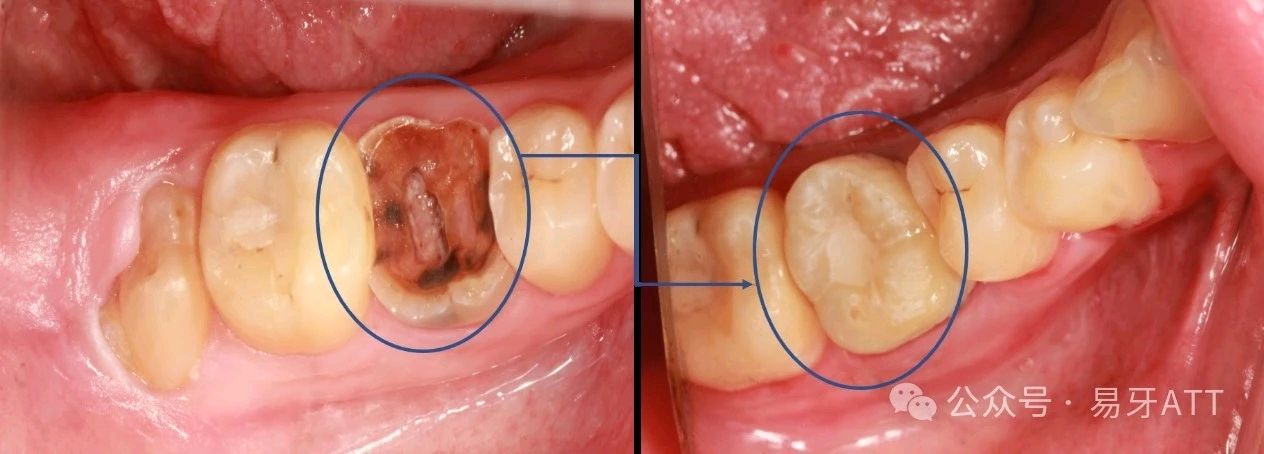

图示为:将同一个个体的右下智齿一直到右下第一磨牙

与活动义齿相比:无需摘戴清洗,图示为:将同一个个体的右下智齿一直到右下第一磨牙无异物感,咀嚼效率高。